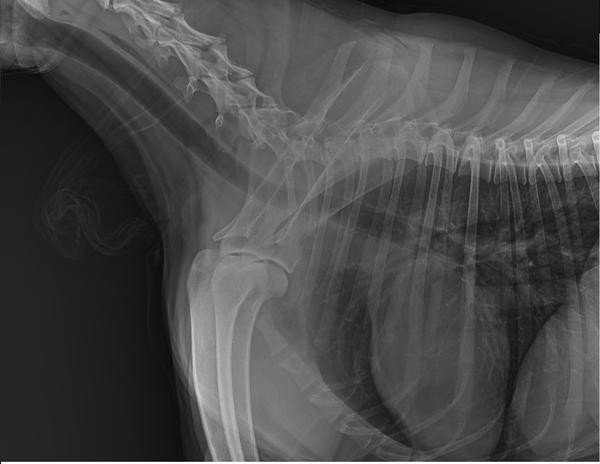

到医院后医院没有仔细看资料,开了7个检查“生化、血常规、4张X光、1组B超、胰腺炎测试、C反、粪便化验”,就是不肯做胃镜检查。宠物主人不好意思反对医生的意见所以7个化验花了2000元。化验结果和我们预料的一样,每一个都没有问题,甚至可以说狗的身体结果是完美的,血常规和生化里没有任何一项指标高或者低(健康狗里都很少),其中2张片子还是照心脏的。